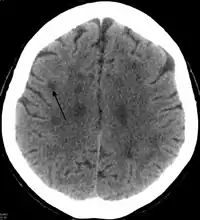

In HDLS, there is enlargement of the lateral ventricles and marked thinning or weakening of cerebral white matter.[6] The loss of white matter is caused by myelin loss. These changes are associated with diffuse gliosis, moderate loss of axons and many axonal spheroids.[1]

Standard MRI scans have been performed on 1.5 Tesla scanners with 5 mm thickness and 5 mm spacing to screen for white matter lesions in identified families. If signal intensities of the MRI scans are higher in white matter regions than in grey matter regions, the patient is considered to be at risk for HDLS, although a number of other disorders can also produce white matter changes and the findings are not diagnostic without genetic testing or pathologic confirmation.[2]

HDLS falls under the category of brain white matter diseases called leukoencephalopathies that are characterized by some degree of white matter dysfunction. HDLS has white matter lesions with abnormalities in myelin sheath around axons, where the causative influences are being continually explored based upon recent genetic findings. Studies by Sundal and colleagues from Sweden showed that a risk allele in Caucasians may be causative because cases identified have thus far been among large Caucasian families.[2]